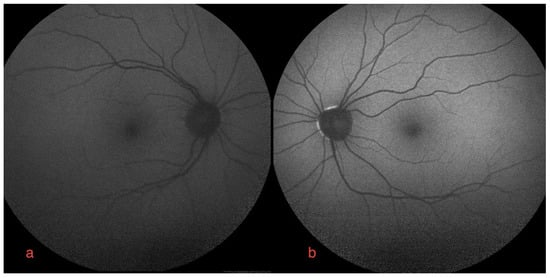

The best-corrected visual acuity was 20/20 in both eyes. An Amsler grid showed no metamorphopsia. Clear diopters were found upon slit lamp microscopy of the anterior segment. Dilated fundoscopy showed no fundus oculi alterations. Macular optical coherence tomography (OCT) (Figure 1a,b) and angiography (OCT-A) were normal.

Figure 1.

Macular optical coherence tomography of right (a,c,e) and left eye (b,d,f): (a,b) baseline right and left eye, normal foveal depression and no subretinal fluid; (c,d) bilateral FGFRAR at one-month follow-up from start of erdafitinib. Foveal serous neuro-epithelial detachment with thickening and high reflectivity of interdigitation zone, disruption of foveal contour with mild increase in central retinal thickening. No sign of increased ChT, no dilated choroidal vessels; (e,f) bilateral FGFRAR relapse at two-months follow-up from start of therapy: subclinical serous detachments with no change in choriocapillaris thickness. Conserved best-corrected visual acuity.

The ophthalmological findings showed bilateral decreased best-corrected visual acuity to 20/25. An absence of the normal foveal reflex was noticed upon fundoscopy. A macular OCT showed bilateral serous neuro-retinal detachment (Figure 1c,d). Fluorescein angiography (FA) was performed and revealed no leakage in either eye and no sign of retinal pigmented epithelium (RPE) alteration (Figure 2a,b). Fundus autofluorescence (FAF) imagining was normal (Figure 3a,b).